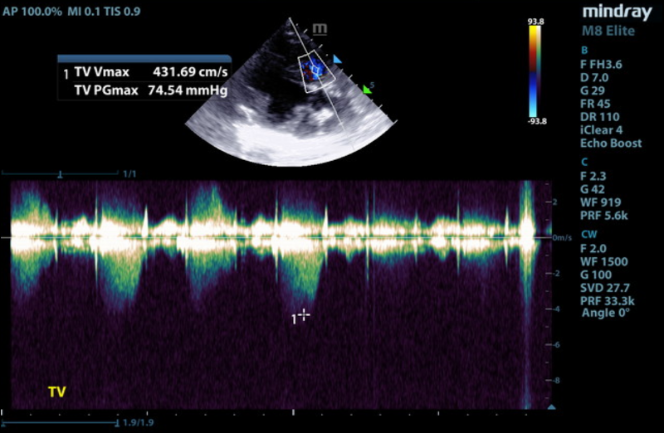

Doppler imaging is the best noninvasive test to diagnose PH. Peak tricuspid regurgitation (TR) velocity and gradient can estimate peak systolic right ventricular pressure. Assuming pulmonic stenosis is not present, TR velocity also correlates with systolic pulmonary arterial pressure. It can be used to classify PH as follows:

1) Mild: 2.8–3.5 m/s, PG 31.4–50 mmHg

2) Moderate: 3.5–4.3 m/s, PG 50–75 mmHg

3) Severe: > 4.3 m/s, PG > 75 mmHg

In this case, the TR Vmax (peak tricuspid regurgitation velocity) was measured at 4.3 m/s on CW Doppler. Plugging this value into the modified Bernoulli equation gives an estimated peak systolic right ventricular (RV) pressure of 74 mmHg. There was no pulmonic stenosis present so peak systolic RV pressure is equal to peak systolic pulmonary arterial pressure of 74 mmHg, moderate to severe pulmonary arterial hypertension.